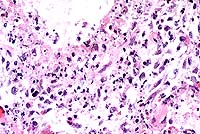

Contributor's Diagnosis and Comments: Liver: Severe chronic diffuse bridging lymphocytic pericholangitis and hepatitis. Pancreas (sections not submitted): Severe chronic diffuse sclerosing lymphoplasmacytic pancreatitis with marked multifocal ductular ectasia.

The findings in this case are consistent with feline progressive cholangitis. According to Lucke and Davies (1984), cats usually present with ascites, jaundice, polyphagia and weight loss; some cats are anorexic. In the same study, cats had unremarkable serum biochemistries with the exception of mildly to moderately increased alkaline phosphatase activities in 12 of 21 cats, and mild to marked increases in conjugated bilirubin in 6 cases.

Gross findings of feline progressive cholangitis consist of a normal to enlarged liver, an enhanced reticular pattern and variably present hepatic nodular change. Histologically, there is prominent lymphocytic infiltration and fewer numbers of other leukocytes. Other changes can include bile duct destruction and/or proliferation, and fibrosis with vascular changes similar to those seen in cirrhosis.

Due to the normal anatomic fusion of the feline pancreatic and biliary ducts proximal to the duodenum, feline hepatobiliary disease may be seen in conjunction with chronic pancreatitis and obstruction. The cat in this case had a severe sclerosing pancreatitis of unknown etiology.

Conference Note: Feline cholangitis/cholangiohepatitis has been described as a disease complex including three characteristic histologic lesions, each presumably reflecting progressive stages of one disease.4 In this report, suppurative cholangitis/cholangiohepatitis, characterized by periportal and hepatic parenchymal infiltration of neutrophils with bile duct hyperplasia, mild fibrosis, and filling of bile ducts with inflammatory cellular debris, was considered the earliest of the three lesions. Long-term inflammation associated with progression of this condition reportedly led to nonsuppurative cholangitis/cholangiohepatitis, with the characteristic histologic findings of lymphocytic and plasmacytic periportal inflammation, bile duct hyperplasia, and periportal fibrosis. Biliary cirrhosis, with severe portal fibrosis, bile duct hyperplasia, nodular hepatic hyperplasia, and a variable degree of chronic inflammation, was presumed to be the end-stage result of long-term cholangiohepatitis in some cats.

In a recent retrospective study, Gagne et al5 described three subclassifications of feline inflammatory liver disease based on the predominant cell type within portal areas, i.e. lymphocytic-plasmacytic, neutrophilic, and mixed. Lymphocytic portal hepatitis was characterized by portal infiltration of lymphocytes and plasma cells, without neutrophils or macrophages. Inflammation was restricted to the portal area and did not extend into hepatic parenchyma. Lymphoid follicles were occasionally found. Bile duct proliferation and portal or portal-bridging fibrosis were present in most cases, but neither biliary epithelial degeneration nor inflammatory cells in bile ducts was seen. Cats with neutrophilic portal hepatitis had primarily neutrophils, with varying numbers of lymphocytes and plasma cells, present within portal areas. Periportal hepatocellular necrosis was a common finding, as was bile duct epithelial degeneration, necrosis, inflammatory cell infiltrate, and duct proliferation. Portal and portal bridging fibrosis was common. Cats with mixed portal hepatitis had approximately equal numbers of lymphocytes/plasma cells and neutrophils. In this third group of cats, associated histologic changes were similar to those with predominantly neutrophilic portal infiltrates. The authors propose using the term lymphocytic portal hepatitis for those cases characterized by lymphocytic/plasmacytic inflammation confined to the portal areas, and that hepatitis characterized by cholangitis and portal neutrophilic infiltrates with or without lymphocytes and plasma cells be termed cholangiohepatitis.